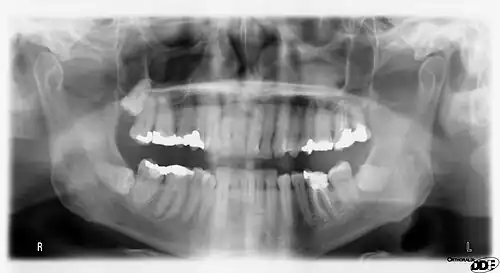

Orthopantomograms (OPTs) are used by health care professionals to provide information on:

- Impacted wisdom teeth diagnosis and treatment planning - the most common use is to determine the status of wisdom teeth and trauma to the jaws.

Panoramic radiographs have the capability to demonstrate a portion of the neck and display atheromas (calcifications in the carotid artery) which are an indication of both local and generalized (systemic) atherosclerosis. Atherosclerosis of the coronary arteries leading to myocardial infarction (heart attack), and atherosclerosis of the carotid artery leading to stroke are the number one and number three most common causes of death in the United States.[6]

Atherosclerosis is attributed to risk factors that include cigarette smoking, hyperlipidemia, obesity, diabetes mellitus, and hypertension (high blood pressure). These factors, however, do not fully account for the risk of disease. Atherosclerosis has been conceptualized as a chronic inflammatory response to endothelial cell injury[24] and dysfunction possibly arising from chronic dental infection. In 2010, using the previously validated Mattila panoramic radiographic index to quantify the totality of dental infection (i.e., periapical and furcal lesions, pericoronitis sites, carious tooth roots, teeth with pulpal caries, and vertical bony defects), Friedlander's group determined that individuals with carotid artery atheromas on their panoramic radiographs had significantly greater amounts of dental infection/inflammation than atherogenic risk-matched controls devoid of radiographic atheromas.[25][26] While the Mattila index had been previously used to relate the extent of dental infection to coronary artery disease, this research is the first to link the full range of dental disease that it measures to panoramic radiographs evidencing calcified carotid artery atherosclerosis.